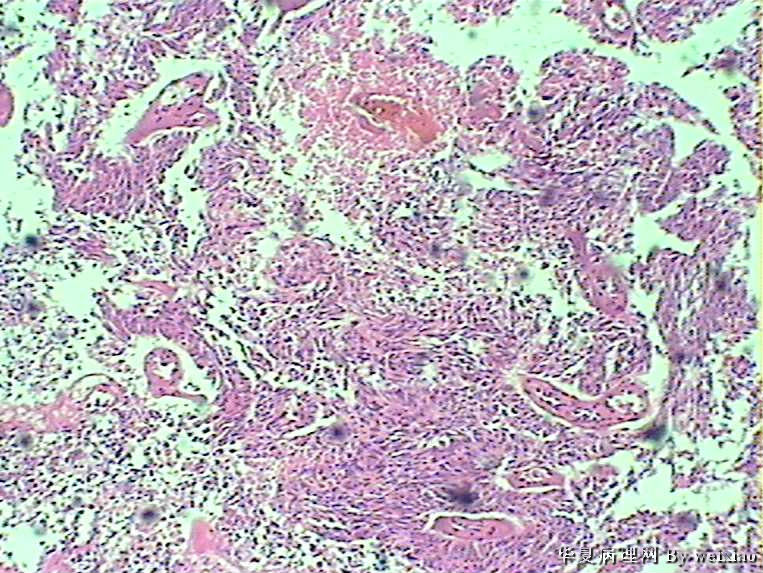

病史:男45岁,头痛2个月,手术所见:额叶占位性病变,与周围正常脑组  织的界限不清。

大体:灰白色碎组织一堆,质软,大小:2.5*1.8*1.3cm

• 额叶肿瘤图4

图4

×参考诊断

胶质母细胞瘤

会诊胶质母细胞瘤

The tumor cells are kind of spindle, need to rule out gliosarcoma, you need to check MRI films, do immunostain for GFAP, and vimentin. The vascular proliferation (VP) supports GBM.

肿瘤细胞呈梭形,血管增生明显,有坏死,符合胶质母。